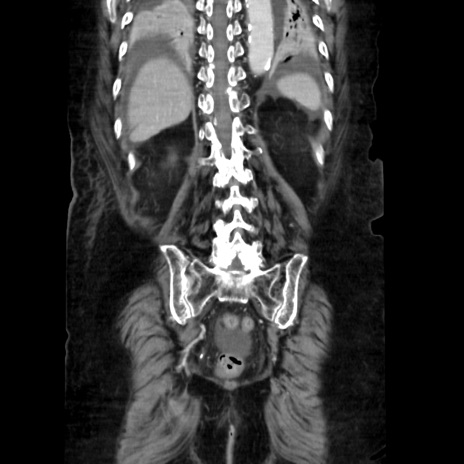

症例40(冠状断像)

【症例】90歳代女性

【主訴】腹痛・嘔吐

【現病歴】 食欲低下、嘔吐があり昨日他院受診。肺炎と診断され入院となる。入院後より腹部全体に圧痛あり。胃管留置され経過みていたが、症状持続するため、

当院転院となる。

【既往歴】胸椎圧迫骨折、胆石症

【身体所見】腹部:中央に激痛あり、圧痛あり、反跳痛不明

【データ】WBC 17100、CRP 18.82

冠状断像